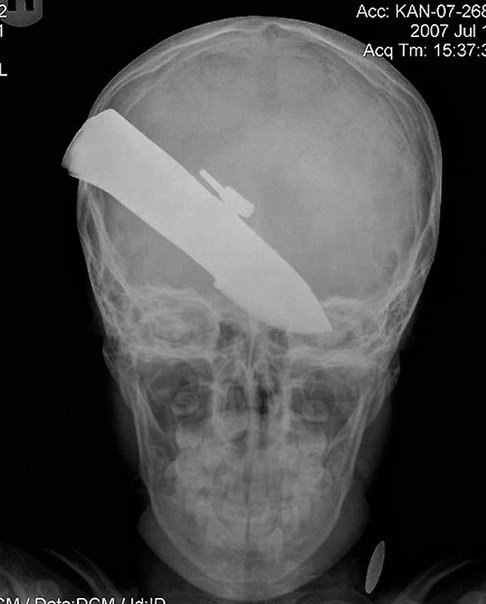

6) Un cuchillo en la cabeza de un niño de 10 años. El paciente sobrevivió